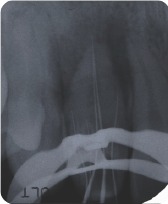

At the initial appointment, tooth #7 was opened and several orifi were located. The canals and invaginations working lengths and sizes were identified and instrumented as the following: far mesial 15.0mmm 20/.04, main canal 18.0mm 40/.04, lingual of main canal 19.0mm 40/.04, distal 1 (blind sac) 10.0mm 30/.02, distal 2 11.0mm 30/.04. Shaping was completed with Flex-O files and GT Series X rotary files. Patency was confirmed throughout and irrigation with both 10 cc 6% NaOCl and 3 cc 17% EDTA for 30 sec in each canal and invagination using passive ultrasonic irrigation with activated with the Newtron P5.

Calcium hydroxide (UltraCal) was placed in all five canals and invaginations and temporized with a sponge and Cavit. After one month, the patient returned to re-irrigate using passive ultrasonic irrigation with the same technique listed above. GT gutta percha cones were sized using the gutta gauge and obturation was completed using the continuous wave technique with AH+ sealer, System B and HotShot. The McSpadden compactor was utilized to custom fill any voids between the two main canals. Vitrebond intraorifice barrier was placed over the gutta percha and the access sealed with Prodigy composite resin. The patient returned after two and a half years for a recall film. The lamina dura and periodontal ligament have healed.

Figure 6: Confirm patency

Figure 7: Periapical film – final

Figure 11: Periapical film of 2.5 year recall